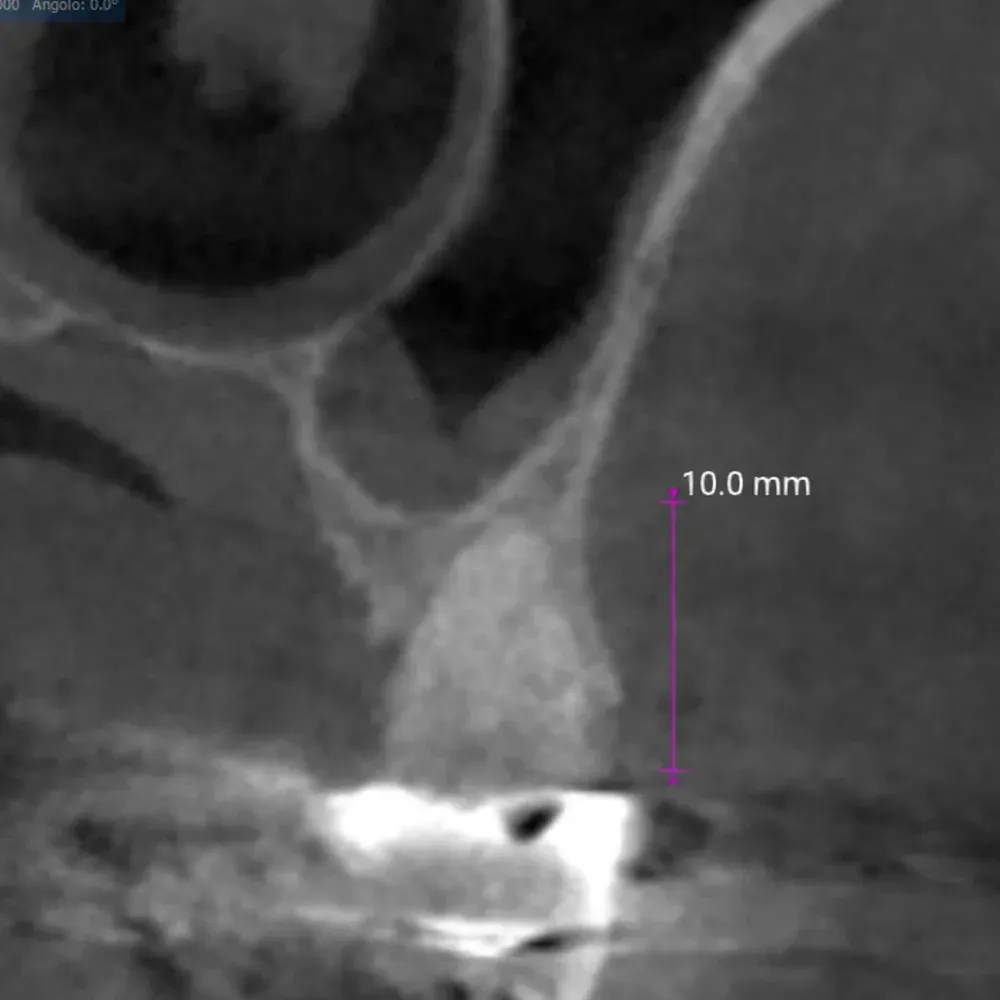

La CBCT dimostra l’anatomia atrofica della zona, con la vicinanza del pavimento del seno mascellare e la significativa perdita di sostanza palatale dovuta all’infezione parodontale.

CBCT di elemento dentario 2.5 affetto da carie e tasca parodontale acuta

CBCT dell’elemento 2.5 con evidenza della vicinanza del seno mascellare e della distruzione del parodonto, soprattutto sul versante palatino.